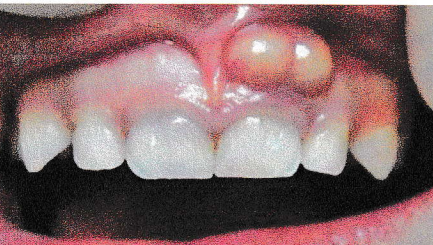

- Une voussure palpable.

- L’absence de réaction aux tests de vitalité.

- Image péri-apicale radioclaire de destruction osseuse.

La croissance des lésions peut entraîner une version, migration, un chevauchement et une mobilité repérable cliniquement. Ponction peut ramener un liquide jaune citrin avec la présence de cristaux de cholestérol.